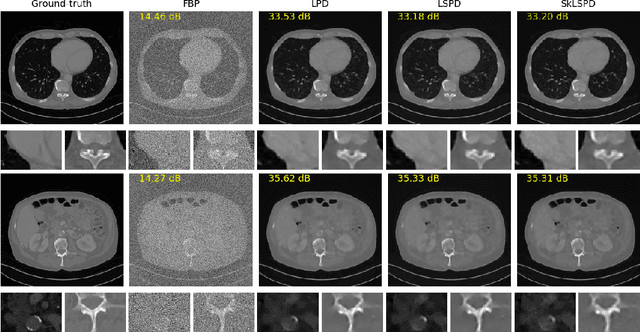

In this work we propose a new paradigm for designing efficient deep unrolling networks using dimensionality reduction schemes, including minibatch gradient approximation and operator sketching. The deep unrolling networks are currently the state-of-the-art solutions for imaging inverse problems. However, for high-dimensional imaging tasks, especially X-ray CT and MRI imaging, the deep unrolling schemes typically become inefficient both in terms of memory and computation, due to the need of computing multiple times the high-dimensional forward and adjoint operators. Recently researchers have found that such limitations can be partially addressed by unrolling the stochastic gradient descent (SGD), inspired by the success of stochastic first-order optimization. In this work, we explore further this direction and propose first a more expressive and practical stochastic primal-dual unrolling, based on the state-of-the-art Learned Primal-Dual (LPD) network, and also a further acceleration upon stochastic primal-dual unrolling, using sketching techniques to approximate products in the high-dimensional image space. The operator sketching can be jointly applied with stochastic unrolling for the best acceleration and compression performance. Our numerical experiments on X-ray CT image reconstruction demonstrate the remarkable effectiveness of our accelerated unrolling schemes.